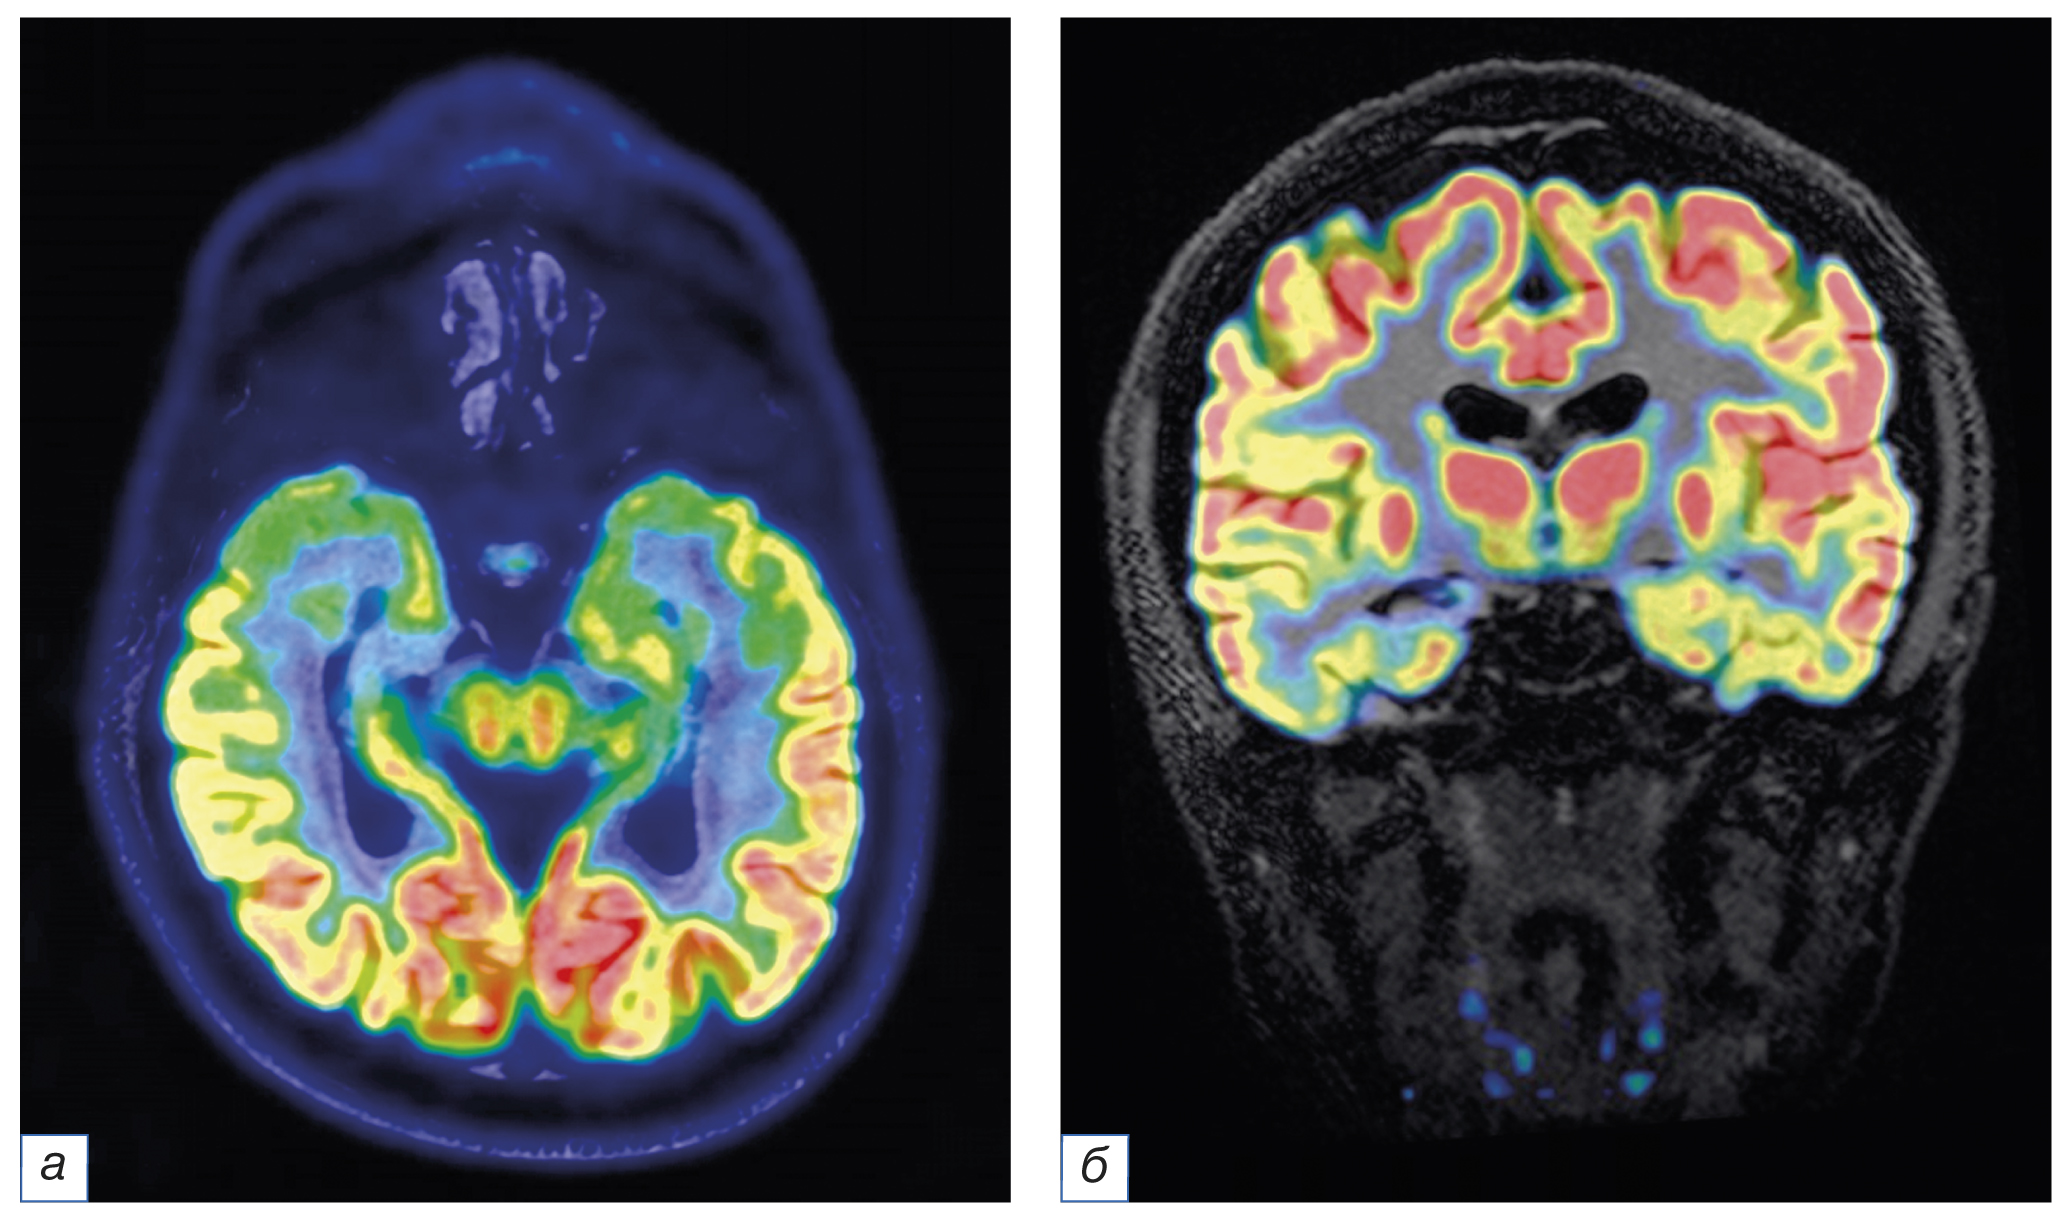

In cases of MR-negative epilepsy, PET can be used to identify hypometabolic areas and revise MRI data in corresponding brain regions, thereby detecting subtle structural changes. This is particularly critical for small focal cortical dysplasias. Although some of the hypometabolism foci detected are not confirmed by MRI data, surgical resection of this area using intracranial EEG in most cases leads to an improvement in clinical symptoms, up to the complete disappearance of seizures. Additionally, in some patients (up to 30%), an MR-negative epileptic focus is visualized contralaterally to EEG data. In such cases, EEG data (intracranial EEG) is crucial [37, 59] (Fig. 4).

Fig. 4. Combined positron emission tomography combined and fLAIR images obtained in the axial (а) and coronal (b) planes. Significant reduction of the 18F-FDG uptake is noted in the right hippocampus head and corpus (courtesy of FSBI «FCMN» FMBA of Russia).